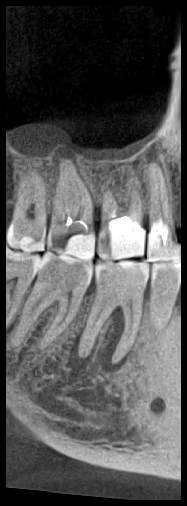

КТ от 28.05.2024

28_05.24(2).jpg.0ffa1febe861106733e1de830afbe6f4.jpg28_05.24-1(2).jpg.9c45d7be16aeed505bd413ce9bc6e69e.jpg28_05.24-2.jpg.a728a7d7e6213c1c8302b43adc89e4d0.jpg28_05.24-4(2).jpg.ac43f3448a3988c7006f74e1d0ce09da.jpg28_05.24-6(2).jpg.dd1fd85c6cc0fcd3d43bd9e71fc0d616.jpg28_05.24-8(2).jpg.885c8cb905445e9308f124fb9e5c616b.jpg28_05.24-9(2).jpg.6cceaaaa1b56d0967482c87b951fbe2d.jpg28.5.24-5(2).jpg.b2d79427a16769c9fd4f0d0911a9db8f.jpg28.5.24-7(2).jpg.f6c17f9820e72dc2708955a65a190b57.jpg28.0524-3(2).jpg.0aa9f153071766a340b428158a94ade8.jpg

Лекарство было извлечено, и каналы запломбированы гуттаперчей. Доктор предупредила, что зуб будет болеть, и прийти я должен после того, как зуб "успокоится", болевые ощущения пропадут. На третий день десна под зубом вспухла, и начала сочиться сукровица. Я решил сделать новое КТ(28.05.2024), и с результатом сходить в другие клиники для консультации. В первой мне сказали, что доктор не должна была начинать лечение, потому, что зуб идет под удаление. Во второй клинике, что попытаться вылечить можно, но изначально были допущены ошибки в лечении, и надо переделывать.

Что-то можно сделать с 46 зубом для сохранения, или он должен быть удален?